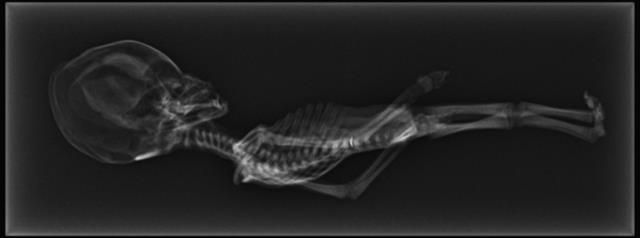

![]() |

Ảnh chụp X-quang xác ướp Atacama. |

Ngoài ra, nó còn có cấu trúc hộp sọ rất dị thường. Nhóm nghiên nhấn mạnh rằng hộp sọ của xác ướp to quá khổ, hay nói cách khác, nếu so sánh với con người, thì phần đầu của xác ướp là quá to so với phần thân.

Đặc điểm dị thường thứ nhất là di thể này chỉ có 10 xương sườn, trong khi ở con người thì thường có 12 cái.

Phần trên cánh tay phải và bên phải phía sau của hộp sọ có một vết nứt, các chuyên gia cho rằng đây có thể là nguyên nhân gây tử vong.

Ngoài ra, từ kết quả chụp CT có thể thấy rõ ràng các cơ quan nội tạng vùng ngực như phổi và một phần cấu trúc vùng tim.